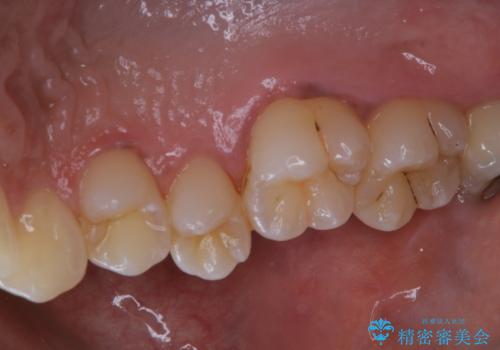

タバコによる着色をPMTCできれいな白い歯に

- タバコによる着色を綺麗にしたいとのことで来院されました。PMTC60分コースを行いました。

PMTCでは、歯の表面の凸凹にミネラルを補給して、ツルツルの表面に仕上げます。定期的にPMTCを行うことにより、歯質の強化になり着色がつきにくい状態になります。

普段の飲食物・歯磨き・生活習慣・喫煙の有無などにより着色の付き具合には個人差があります。どれくらいの頻度で行うことがベストかは、その都度担当の歯科衛生士とご相談します。